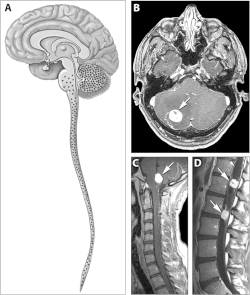

![]() | |

| Locations of the main types of cysts and tumors in Von Hippel–Lindau disease.[2] | |